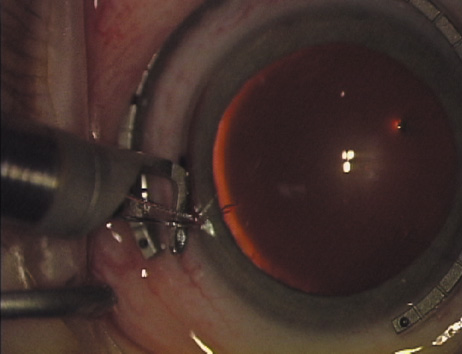

Case 2 is a 79-year-old woman who presented with a very dense left cataract. Her refraction was recorded at −2.25 +2.75 × 125 with a difficult end point. Her manual keratometry and topography measurements were consistent and revealed slightly less than 1.75 D at 120 degrees. Because of the questionable refraction, greater value was placed on the corneal measurements. Based upon the cataract nomogram, the plan was for paired LRIs of 40 degrees to be placed over the steep 120-degree axis (Figs. 1219).

Fig. 12. In this left eye, the steep meridian is at the 120-degree axis and has been delineated by opposing limbal marks. The upper left hand ink mark represents the 6:00 position for orientation. (Reprinted from Hardten DR, Lindstrom RL, Davis EA. Phakic Intraocular Lenses: Principles and Practice. Thorofare, NJ: SLACK Incorporated, 2004, with permission.)

Fig. 13. The incision is begun 20-degrees to one side of the centering mark. (Reprinted from Hardten DR, Lindstrom RL, Davis EA. Phakic Intraocular Lenses: Principles and Practice. Thorofare, NJ: SLACK Incorporated, 2004, with permission.)

Fig. 14. The incision is completed. (Reprinted from Hardten DR, Lindstrom RL, Davis EA. Phakic Intraocular Lenses: Principles and Practice. Thorofare, NJ: SLACK Incorporated, 2004, with permission.)

Fig. 15. Total arc length equals 40 degrees. (Reprinted from Hardten DR, Lindstrom RL, Davis EA. Phakic Intraocular Lenses: Principles and Practice. Thorofare, NJ: SLACK Incorporated, 2004, with permission.)

Fig. 16. The starting point of the opposing incision is determined. (Reprinted from Hardten DR, Lindstrom RL, Davis EA. Phakic Intraocular Lenses: Principles and Practice. Thorofare, NJ: SLACK Incorporated, 2004, with permission.)

Fig. 17. The opposing incision is begun. (Reprinted from Hardten DR, Lindstrom RL, Davis EA. Phakic Intraocular Lenses: Principles and Practice. Thorofare, NJ: SLACK Incorporated, 2004, with permission.)

Fig. 18. The incision is completed. (Reprinted from Hardten DR, Lindstrom RL, Davis EA. Phakic Intraocular Lenses: Principles and Practice. Thorofare, NJ: SLACK Incorporated, 2004, with permission.)

Fig. 19. The temporal single-plane clear corneal incision is placed independent of the LRIs. (Reprinted from Hardten DR, Lindstrom RL, Davis EA. Phakic Intraocular Lenses: Principles and Practice. Thorofare, NJ: SLACK Incorporated, 2004, with permission.)